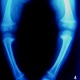

Искривление голеней имеет штыкообразный вид и определяется сразу же под коленным суставом. Вершина искривления обращена кнаружи. На уровне верхнего метафиза большеберцовой кости у всех больных определяется клювовидный выступ. Рано появляется выстояние головки мало-берцовой кости. Диафизы обеих костей голени всегда остаются прямыми. Обязательным и постоянным симптомом заболевания является внутренняя ротация голеней и часто рекурвация. Степень внутренней ротации может колебаться от 20 до 85°. По величине варусного искривления деформации голени могут быть разделены на три степени. К заболеваниям легкой степени относятся искривления во фронтальной плоскости с углом вируса от 5 до 13>, межмыщелковым расстоянием в 2-5 см. При заболевании средней степени величина угла вируса составляет 15-30°, а межмыщелковое расстояние равно 10-12 см. Тяжелые степени деформации характеризуются варусным углом от 30 до 55° и межмыщелковым расстоянием до 19-21 т. Из сопутствующих изменений при болезни Эрлахера-Блаунта выявляются понижение тонуса и атрофия мыши голеней. Почти у всех пациентов отмечается плоскостопие. Вил больных характерен (рис. 56). Они низкорослы из-за потери анатомической длины больше-берцовых костей, с более или менее выраженной варусной деформацией ног. Поэтому диагностика заболевания несложна. Рентгенологическая картина болезни Эрлахера-Блаунта довольно типична и представлена следующими признаками. 1. Отмечается искривление большеберцовой кости на уровне проксимального отдела метафиза, часто вблизи границы с эпифизом, что определяется в виде клювовидного костного выступа. 2. Деформация эпифиза - постоянный рентгенологический признак заболевания. Во всех случаях внутренняя часть суставной поверхности его располагается косо под углом 30-45° в дистальном направлении; она всегда деформирована - равномерно вогнута, нередко повышенно минерализована. Внутренний отдел эпифиза часто уменьшен по высоте почти в 2-3 раза. Возможна краевая фрагментация. 3. Как правило, с внутренней стороны сустава расширяется эпифизарная ростковая зона в виде раструба кости. Костно-замыкательные пластинки здесь нечеткие, расплывчатые. В последующем отмечается преждевременное закрытие хрящевых метафизарных зон роста. 4. Наблюдается компенсаторное утолщение кортикального слоя больше-берцовой кости по внутренней поверхности, с усилением внутрикостного рисунка. 5. Изменяется положение малоберцовой кости (наслаивается на больше-берцовую кость) из-за торсии голени.

Рахит. Болезнь Блаунта - поражение изолированное, а здесь варусная еформация голеней и бедер.